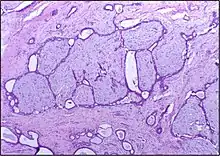

![]() | Cystic hyperplasia of endometrium | Micrograph showing cystic hyperplasia of endometrium. Cystically dialated glands are lined by proliferative type of epithelium. Stroma also resembles proliferative phase. No atypia is seen in the cells. | Category: Histopathology of hyperplasia endometrium | Cystic hyperplasia |